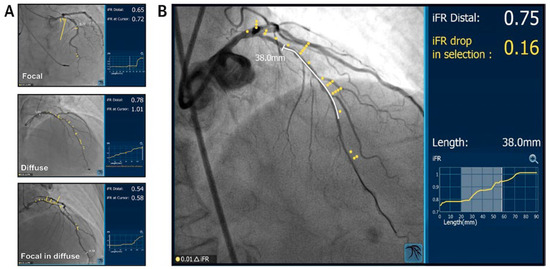

An 88-year-old man with a history of transient ischaemic attack, chronic kidney disease and primary hypertension presented with dyspnoea and was found to have large bilateral pulmonary emboli on a computedtomography angiogram of the chest [...]